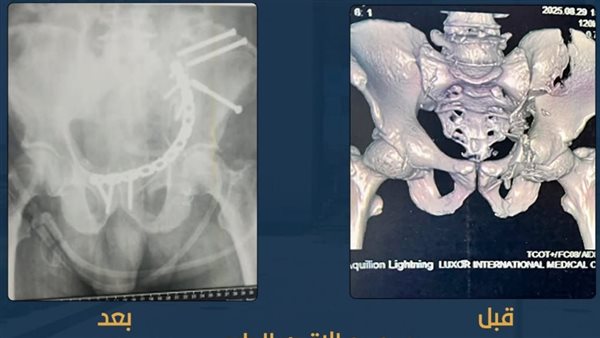

عظامه متفتتة.. نجاح عملية جراحية دقيقة لتثبيت كسور بالحوض لمريض بمجمع الأقصر الطبي الدولي

أعلن مجمع الأقصر الطبي الدولي التابع لهيئة الرعاية الصحية، نجاح عملية جراحية معقدة لتثبيت كسور الحوض لمريض كان يعاني من تفتت كامل في عظام الحوض، حيث أُجريت العملية باستخدام الشرائح والمسامير لتثبيت العظام وإعادتها إلى وضعها الطبيعي.

قاد العملية نخبة من أطباء جراحة العظام والتخدير، مدعومين بفريق تمريض مدرَّب، حيث جرى التدخل الجراحي بدقة عالية مع اتخاذ كافة الإجراءات الطبية اللازمة لضمان استقرار حالة المريض.